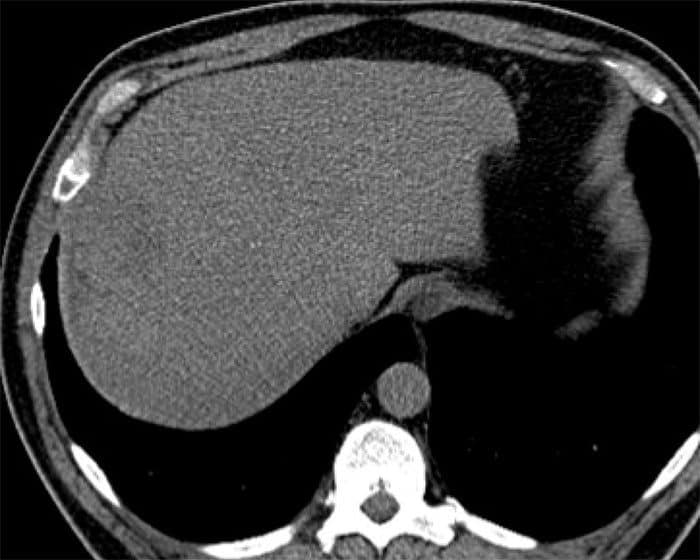

Sán lá gan

» Thông tin: Nam giới – 52 tuổi.

» Lâm sàng: Kiểm tra sức khỏe.